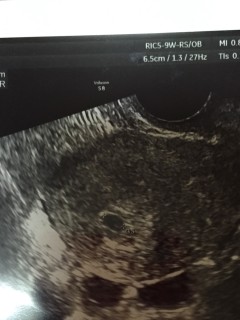

エコーの画面が移った瞬間にすぐにわかりました!胎嚢6.7mmと言われました。 待ちに待った妊娠でとても嬉しかったです!